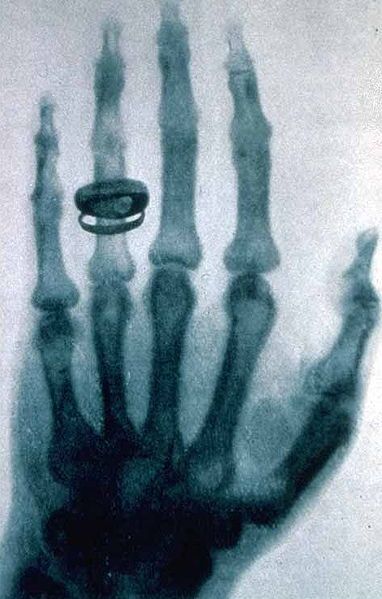

1895年德國物理學家威廉·康拉德·倫琴發現X射線(一般稱X光)以來,開啟了醫學影像嶄新的一頁,在此之前,醫師想要了解病患身體內部的情況時,除了直接剖開以外,就只能靠觸診,但這兩種方法都有一定的風險。

醫學影像是指為了醫療或醫學研究,對人體或人體某部分,以非侵入方式取得內部組織影像的技術與處理過程。它包含以下兩個相對獨立的研究方向:醫學成像系統(medical imaging system)和醫學圖像處理(medical image processing)。前者是指圖像行成的過程,包括對成像機理、成像設備、成像系統分析等問題的研究;后者是指對已經獲得的圖像作進一步的處理,其目的是或者是使原來不夠清晰的圖像復原,或者是為了突出圖像中的某些特征信息,或者是對圖像做模式分類等等。